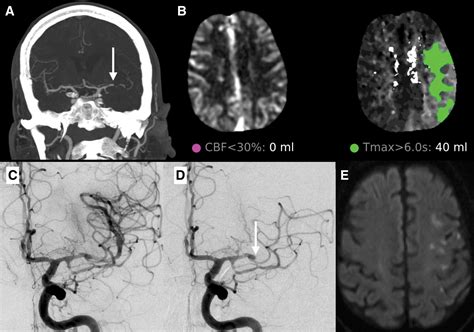

• large vessel occlusion

• lvo in stroke

• lvo stroke brain